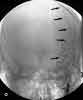

Figure 1

The initial CT scan of the brainshowed a linear hyperdensity in theregion of the left middle cerebral artery,which indicated thrombus formation(Figure 1). An area of cerebral edemawas noted in the region with a smalleffacement from left to right. A cerebralangiogram performed 6 hours after theCT scan revealed a complete dissectionof the left internal carotid artery (ICA)from the second cervical segmentcraniad (Figure 2). A follow-up CTbrain scan 24 hours later demonstrateda large, left middle cerebral arteryischemic infarction with midline shiftingand evidence of left uncal herniation(Figure 3).